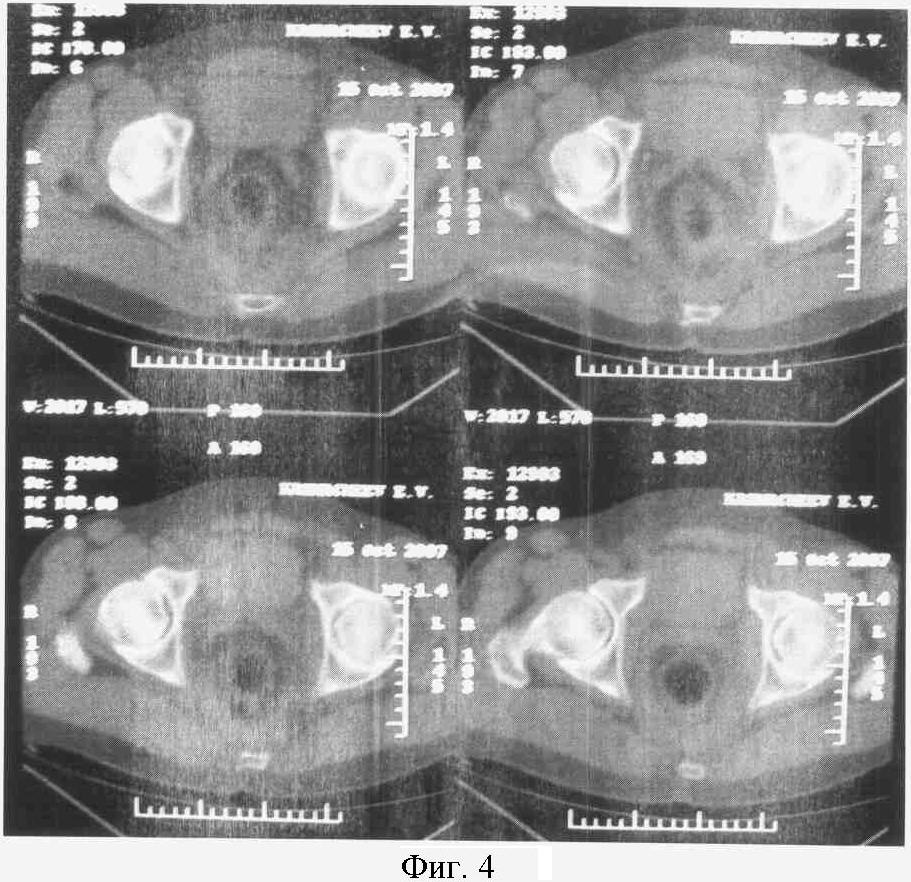

На фиг.2. представлен КТ срез на уровне нижней трети головки бедра.

Справа: 1-я стадия коксартроза с локализацией участков компрессии в заднем отделе сустава (1).

Слева: 3-я стадия коксартроза с кистевидной перестройкой с локализацией участков компрессии в заднем (1) и переднем отделах сустава (2).